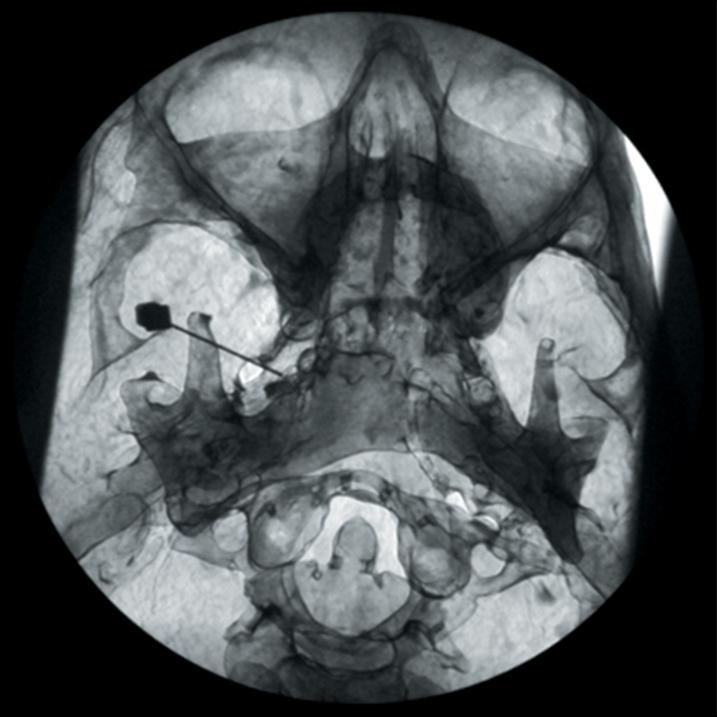

The Regional Anaesthesia Simulation Manikin has been designed by a Consultant Anaesthetist at the Manchester and Salford Pain Centre for training anaesthetists in correct needle placement in Nerve Blocks for pain management.

- Orientation of image and identification of appropriate radiographic landmarks

- The end point of simulation is the correct radiographic appearance

- The manikin consists of a specially coated plastic human skeleton, head covered in artificial skin and fabric covered torso, on which trainees can practice the placement of needles under X-ray image intensifier control

- The X-ray density of the manikin is low so that the doses of radiation used during simulated procedures are reduced